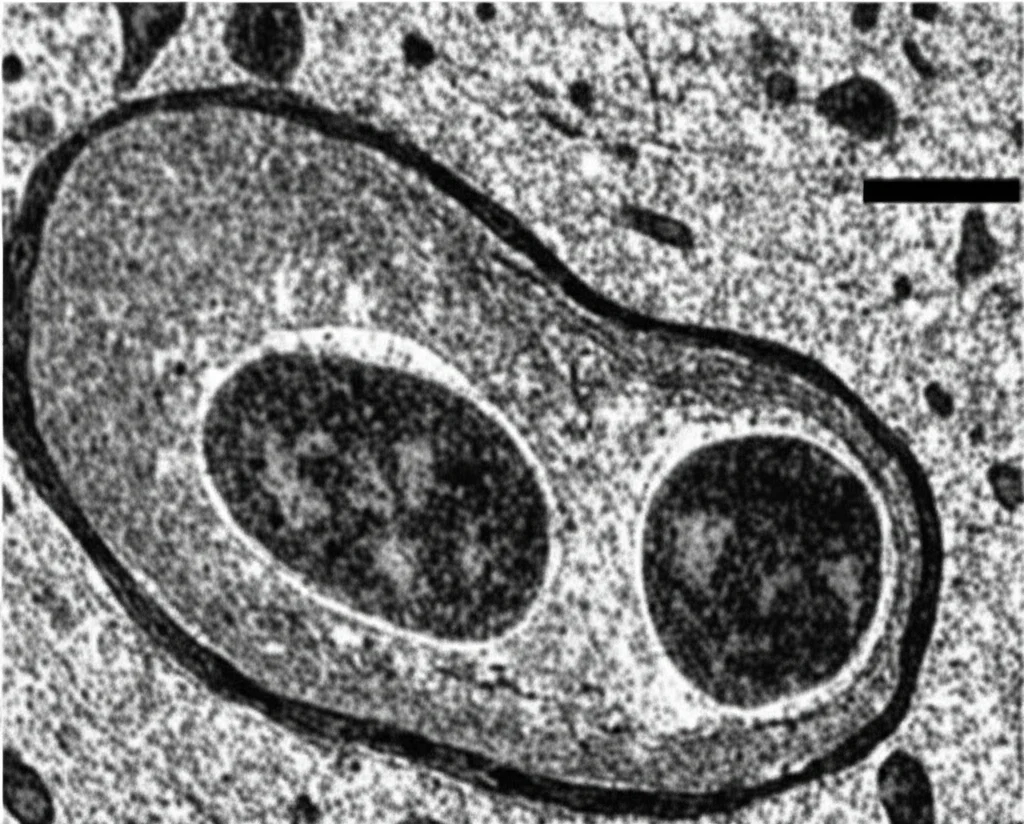

Andando ancora più a fondo, con la microscopia elettronica (che ci permette di vedere dettagli piccolissimi), abbiamo esaminato i mitocondri negli assoni dei topi infettati. Nei topi normali infettati con JEV, i mitocondri apparivano danneggiati: gonfi, con le loro strutture interne (le creste) ridotte o scomparse. Al contrario, nei topi trattati con SIC4 o nei topi Sarm1 KO, i mitocondri mantenevano un aspetto molto più sano, quasi normale, nonostante l’infezione. Questo suggerisce che il danno mitocondriale SARM1-dipendente sia un meccanismo chiave attraverso cui i virus neurotropici portano alla degenerazione assonale.